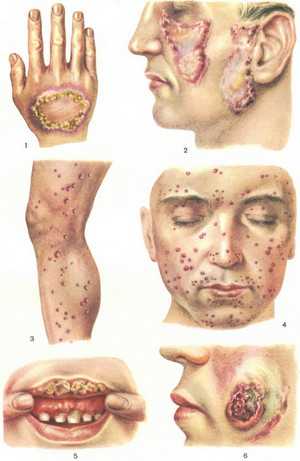

Кожный синдром

Наиболее часто встречается типичная волчаночная «бабочка» – покраснение кожи в области скул и спинки носа.

Есть несколько вариантов поражения кожи:

- Васкулитная (сосудистая) бабочка. Характеризуется нестойким разлитым покраснением кожи лица, с синевой в центре, усилением проявлений под действием холода, ветра, волнении, ультрафиолета. Очаги покраснения бывают как плоскими, так и приподнятыми над поверхностью кожи. После заживления рубцов не остается.

- Множественные высыпания на коже из-за фотосенсибилизации. Возникают на открытых участках тела (шея, лицо, декольте, руки, ноги) под воздействием солнечных лучей. Сыпь проходит без следа.

- Подострая красная волчанка. Зоны покраснения (эритемы) появляются после пребывания на солнце. Эритемы приподняты над поверхностью кожи, могут иметь форму кольца, полумесяца, почти всегда шелушатся. На месте пятна может оставаться участок депигментированной кожи.

- Дискоидная красная волчанка. Сначала у больных появляются маленькие красные бляшки, которые постепенно сливаются в один большой очаг. Кожа в таких местах тонкая, в центре очага отмечается избыточное ороговение. Появляются такие бляшки на лице, волосистой части головы, разгибательных поверхностях конечностей. На месте очагов после заживления остаются рубцы.

К кожным проявлениям могут присоединяться выпадение волос (вплоть до полного облысения), изменения ногтей, язвенный стоматит.

В начале СКВ поражения кожи беспокоят только 20% пациентов. У 60% больных симптомы проявляются позже. У некоторых людей они совсем не возникают. Признаки болезни можно увидеть на лице, шее и плечах. На спинке носа и щеках появляется сыпь в виде красноватых бляшек с шелушением, напоминавшая в прошлом волчьи укусы. Её называют «волчаночной бабочкой», поскольку она выглядит как это насекомое. У больного повышается чувствительность кожи к ультрафиолету.

У некоторых людей при волчанке выпадают волосы в височных областях и ломаются ногти. Слизистые поражаются в 25% случаев. Появляется люпус-хейлит, характеризуемый плотным отёком губ в виде сероватых чешуек. По кайме могут возникнуть мелкие язвы красного или розового цвета. Кроме того, поражается слизистая оболочка полости рта.

- Кожа, ногти и волосяной покров

Вовлечение в патологический процесс кожи – наиболее частые симптомы красной волчанки у женщин, возникновение которых связано с каким-то причинным фактором: длительное воздействие солнечного света, пребывание на морозе, психоэмоциональное потрясение (см. крапивница — симптомы, лечение, аллергия на солнце).

Весьма характерно для СКВ покраснение участков кожи возле носа и щек, по форме похожее на крылья насекомого бабочки. Помимо лица, эритема появляется на открытых участках кожи – верхних конечностях, зоне декольте. Эритема склонна к периферическому разрастанию.

При дискоидной красной волчанке кожная эритема сменяется воспалительным отеком. Эта область постепенно уплотняется и через некое время атрофируется с формированием рубца. Очаги дискоидной волчанки встречаются на разных участках тела, что свидетельствует о диссеминации процесса.

Еще один симптом СКВ – капиллярит, который проявляется покраснением, отеком и многочисленными кровоизлияниями в виде мелких точек, локализованных на подушечках пальцев рук, подошвах и ладонях.

Поражение волос при СКВ проявляется постепенным частичным или полным облысением (см. причины выпадения волос у женщин). В период обострения характерно изменение структуры ногтей, часто приводящее к атрофии околоногтевого валика.

Очаговое облысение или генерализованное, кожный зуд и крапивница — являются самыми характерными симптомами СКВ. Кроме кожных проявлений больных беспокоят головные боли, боли в суставах, изменения функции почек и сердца, перепады настроения от эйфории до агрессии.

- Слизистые оболочки

Чаще страдают слизистые рта и носа: появляются покраснения, образуются эрозии (энантемы) на слизистой и мелкие язвы во рту (см. мази от стоматита, афтозный стоматит у взрослых, лечение). При образовании трещин, эрозий и изъязвлений красной каймы губ возникает люпус-хейлит. Очаги поражения становятся в виде плотных синюшно-красных бляшек, которые болезненны при приеме пищи, склонны к изъязлениям, имеют четкие границы и покрыты иногда отрубевидными чешуйками.

Главным признаком СКВ считается волчаночная «бабочка», которая может проявляться в четырех вариантах, в зависимости от степени выраженности и стойкости воспалительного процесса:

- Сосудистая бабочка. Характерной особенностью является появления в середине лица нестойких пульсирующих покраснений с синюшным оттенком. Симптоматика усиливается от воздействия внешних факторов – ветра, холода или солнца.

- Бабочка, образованная в результате слияния стойких эритематозно-отечных пятен. Наблюдаются ороговения кожи в местах поражения.

- Бабочка, которая образовывается в результате слияния ярко-розовых пятен. Отечность пятен сильно выделяется на фоне общей отечности лица, особенно век.

- Бабочка в виде рубца, образованного из элементов дискоидного типа с четко выраженной атрофией.

В некоторых случаях эритематозные высыпания могут локализироваться на лбу, мочках ушей, шее, губах, волосистой части головы или в области «декольте».

Кожные проявления системной красной волчанки могут также локализироваться на пальцах рук и ног в виде васкулитов или сосудистых звездочек. Реже их можно встретить на подошвах и ладонях. Еще реже из-за СКВ могут образовываться язвы, пролежни или деформация ногтей.